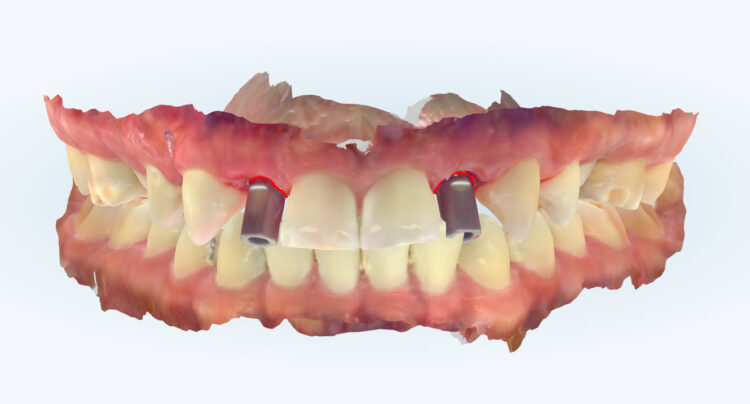

A CBCT scan was taken using a Morita X800. This dataset was imported into the planning software, where it was merged with the STLs of the anatomically correct diagnostic digital wax-up and modules.  With the anatomically correct diagnostic wax-up, there was no ambiguity regarding planning the implant position, angle and depth with precision. I like to plan these types of cases myself, but it is possible to outsource the planning stage for clinicians who are new to the process and looking to increase their workflow efficiency. For this case, I wanted to build up the gingival thickness in order to improve the papillae around the implant sites. The surgical plan, therefore, included soft tissue grafting.

On the day of surgery, a split-thickness envelope flap was raised. Two CONELOG® Progressive-Line implants were placed through the surgical guide in the pre-determined lateral incisor positions. Soft tissue augmentation was performed simultaneously with the implant placement, and the site was sutured and closed without tension. The implants were immediately loaded using provisional crowns that were pre-fabricated in the lab.

The CONELOG implants were selected because they provide a very stable connection and feature a geometry that facilitates high primary stability, which is important when placing immediate implants. They also integrate very successfully – we have had better results with these implants than with other products that are available. I also appreciate the simplicity of the keyless guided surgery kit.